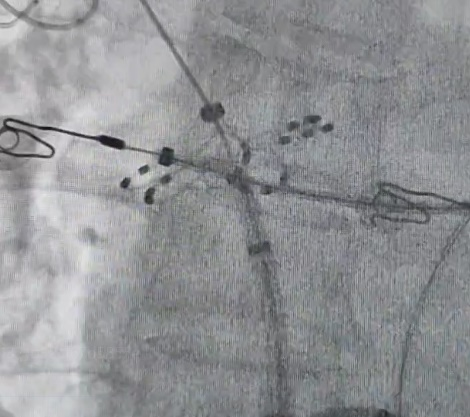

在华西医院胡宏德教授的指导下,团队使用国产花瓣状脉冲电场消融导管,采用“231”消融策略,在LSPV、LIPV、RSPV和RIPV的口部和前庭进行脉冲消融,实施肺静脉“双重隔离”。

口部“网篮状”消融

前庭“花瓣状”消融